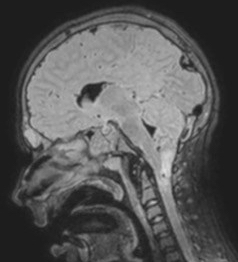

l’engagement tonsillaire chronique peut résulter d’une hypertension intracrânienne prolongée, en rapport avec un trouble hydrodynamique. on rencontre ainsi des Chiaris associés à la pseudo-tumor cerebri, aux craniosténoses, etc. il existe ainsi un spectre de pathologies hydrauliques intracrâniennes avec des recoupements symbolisés sur le diagramme ci-dessus.

inversement, une hypotension liée à une fuite rachidienne conduit à une aspiration des tonsilles vers le bas, ce qui est une complication classique des valves lombo-

péritonéales ; de la même façon, une ponction lombaire peut récompenser de façon dramatique une malformation de Chiari.